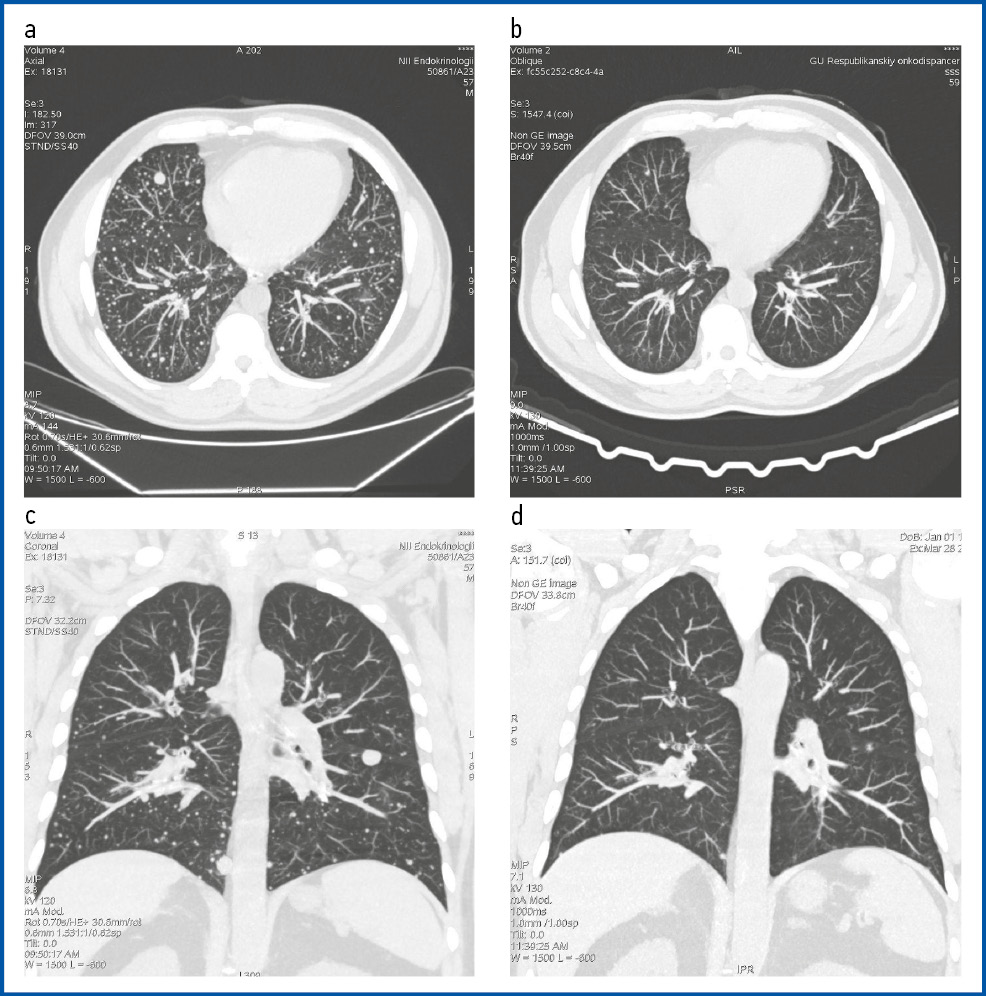

Через 6 мес (в сентябре 2023 г.) при динамической КТ органов грудной клетки без контрастирования отмечалась отрицательная динамика в виде увеличения размеров отдельных очагов. В обоих легких сохранялись множественные солидные очаги с четкими ровными контурами, расположенные интрапаренхиматозно и субплеврально, размером от 2 до 15 мм (рис. 1, а, c). Увеличение в размере отдельных очагов до 20% в течение 9 мес (по сравнению с КТ от января 2023 г.) соответствовало одному из критериев РЙР (прогрессирование очагов, несмотря на проведение терапии радиоактивным йодом).

На фоне комбинированной терапии по данным КТ-контроля от марта 2024 г. отмечалась положительная динамика в виде уменьшения размеров большинства очаговых образований легких до 40% (см. рис. 1, b, d).

Рис. 1. КТ органов грудной клетки без внутривенного контрастирования: a – аксиальный срез до ТТ (сентябрь 2023 г.); b – аксиальный срез через 3 мес после редифференцировки опухоли и курса РЙТ (март 2024 г.); c – корональный срез до ТТ (сентябрь 2023 г.); d – корональный срез через 3 мес после редифференцировки опухоли и курса РЙТ (март 2024 г.).

Fig. 1. Non-enhanced chest computed tomography: a – axial section before targeted therapy (September 2023); b – axial section 3 months after tumor redifferentiation and a course of radioactive iodine therapy (March 2024); c – coronal section before targeted therapy (September 2023); d – coronal section 3 months after tumor redifferentiation and a course of radioactive iodine therapy (March 2024).